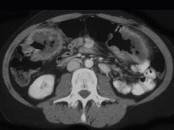

问题 男,55岁,腹部胀痛不适1月余,CT检查如图,最可能的诊断是()

选项 A.结肠结核 B.结肠淋巴瘤 C.结肠转移瘤 D.假膜性结肠炎 E.横结肠癌

答案 E